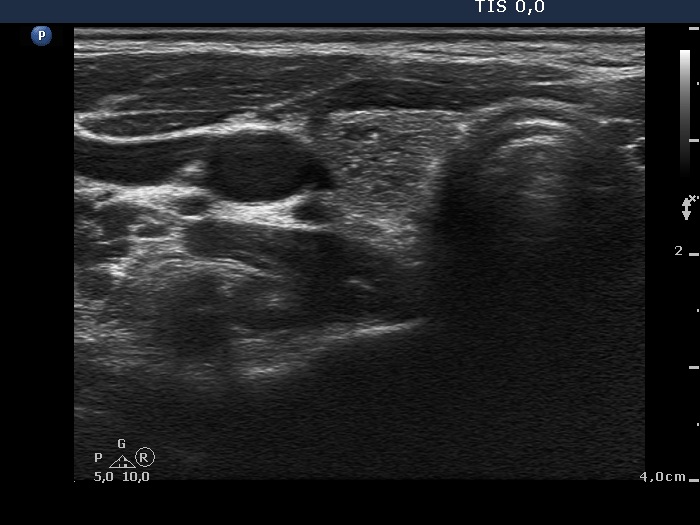

Follicular adenoma (histological diagnosis) - case cons 024 |

Benign hyperplastic nodules (histological diagnosis) - case 1091 |

Beside the very tiny granules and lines we find larger hyperechogenic granules, while the presence of similarly bright lines is spared. It is therefore ambiguous whether these figures are punctate echogenic foci or presentation of a connective tissue.

Several bright granules have dorsal pale tail therefore these and probably also the other granules lacking a tail belong to a comet-tail artifact subgroup.